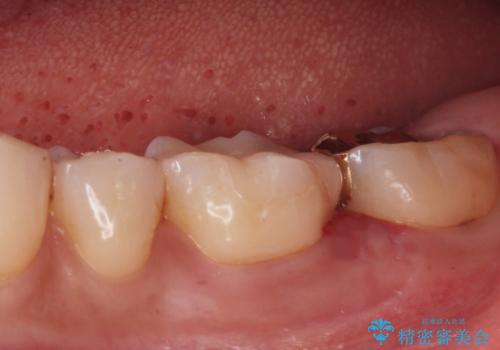

- 歯が黒くて虫歯じゃないかと心配して来院。

過去にプラスチックの樹脂で治療されており、歯とプラスチックの隙間から虫歯が進行していました。

拡大鏡下で虫歯を除去し、詰め物にて治療しました。

一番奥の歯は歯の高さが足りない、噛む面を覆う面が広くなってしまい、セラミックの詰め物だと割れるリスクが高くなってしまうので手前はセラミックインレー奥の歯はゴールドインレーにて治療しました。